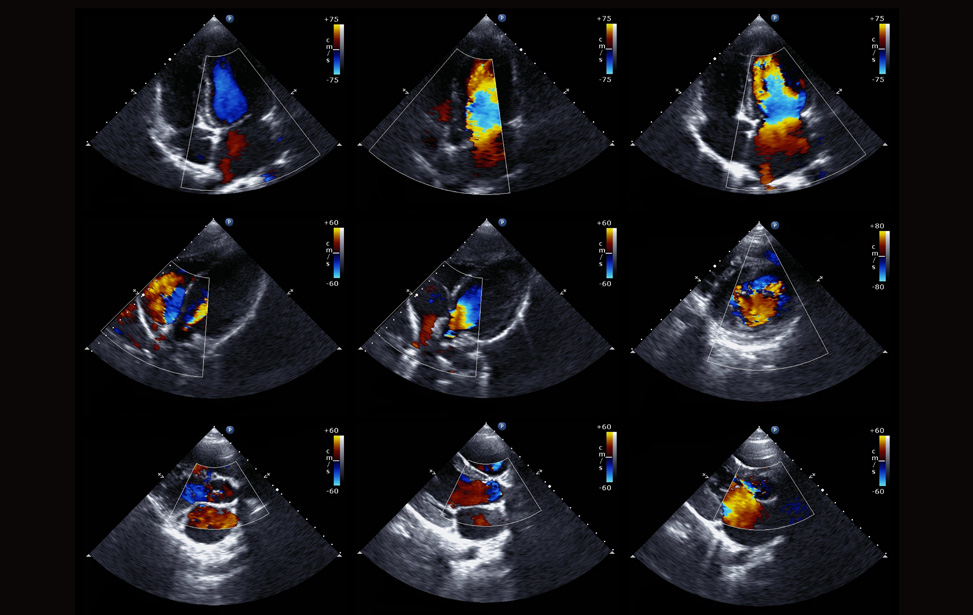

2D/4D ECHO COLOR DOPPLER

Color Doppler uses the principle of the variation of pitch, with the velocity....